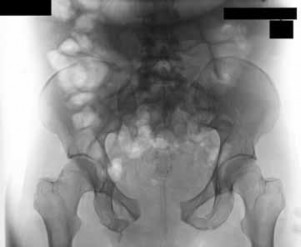

Figure 7Figure 7 is the pelvic radiograph of a 33-year-old man involved in a high-speed automobile crash. Examination reveals a blood pressure of 90/50 mm Hg and a pulse rate of 120/min. Radiographs of the chest and lateral cervical spine are normal. A CT scan of the abdomen does not reveal any intraabdominal bleeding. What is the most appropriate management for the pelvic fracture?